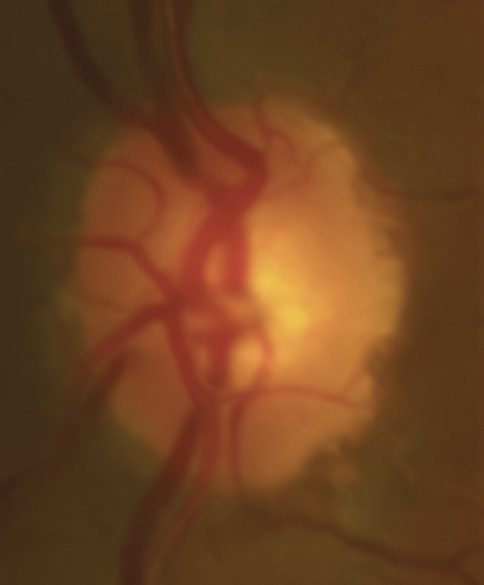

A 46-year-old African American male presents for glaucoma quarterly monitoring. Medical history is positive for hypertension controlled with 50 mg hydrochlorothiazide and reports no diagnosis of diabetes mellitus or known drug allergies. Ocular history is positive for progressive myopia bilaterally and pigment dispersion syndrome converting to pigmentary glaucoma right eye mild, left eye moderate with treatment initiated in September of 2016. The pigmentary glaucoma was treated with 0.005% latanoprost in both eyes every evening. There was positive family history of glaucoma (patient’s father). Best corrected visual acuity was measured at 20/25 in each eye. Pupillary assessment revealed a stable 1+ afferent pupillary defect in the left eye. Confrontation fields were full to finger count in the right eye and superonasal constriction in the left eye. Extraocular motilities were full with no restrictions or report of diplopia in both eyes. Slit lamp examination is remarkable for a Krukenberg spindle (Figure 4) bilaterally and a Zentmeyer line (Figure 5) in the left eye. Intraocular pressures at 3:30 pm via GAT measured 18 mmHg right eye, 23 mmHg left eye. Gonioscopy was performed and revealed open angles to ciliary body with a concave iris configuration and 4+ trabecular meshwork pigmentation (Figure 6) and the posterior corneal surface. There was no pigment attached to the anterior lens surface. The highest recorded intraocular pressures prior to treatment were 27 mmHg right eye & 35 mmHg left eye. CCT measured 554 microns in the right eye and 538 microns left eye. Optic nerve head assessment revealed bilateral intact neuroretinal rims with vertical elongation greater in the left eye than the right with inferior neuroretinal rim thinning in the left eye (Figure 7).

Bild 7: Fall 2 – (a) Sehnervenkopf OD, (b) Sehnervenkopf OS

CD ratios were estimated horizontally/vertically as 0.4/0.5 right eye, 0.6/0.8 left eye. Repeat testing of 24-2 Humphrey Visual Fields (HVF) (Figure 8) and optic nerve head optical coherence tomography (OCT) (Figure 9) were obtained.